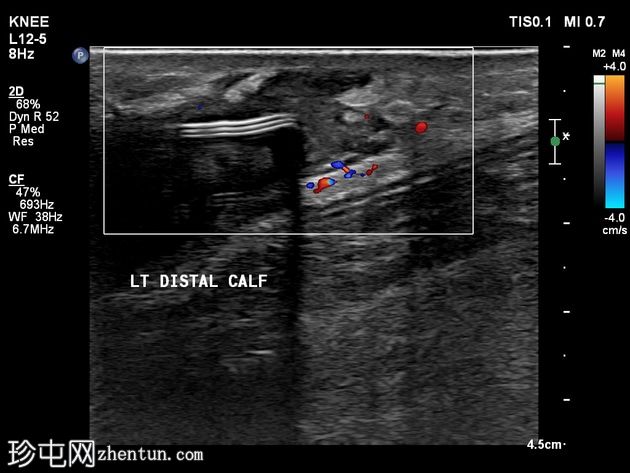

超声

横断面

可见皮下、肌外软性硅胶小腿植入物。植入物包膜局部破裂/撕裂,局部凝胶渗漏,并出现炎症反应,多普勒超声检查显示充血。未见边界清晰或包膜完整的脓肿形成。